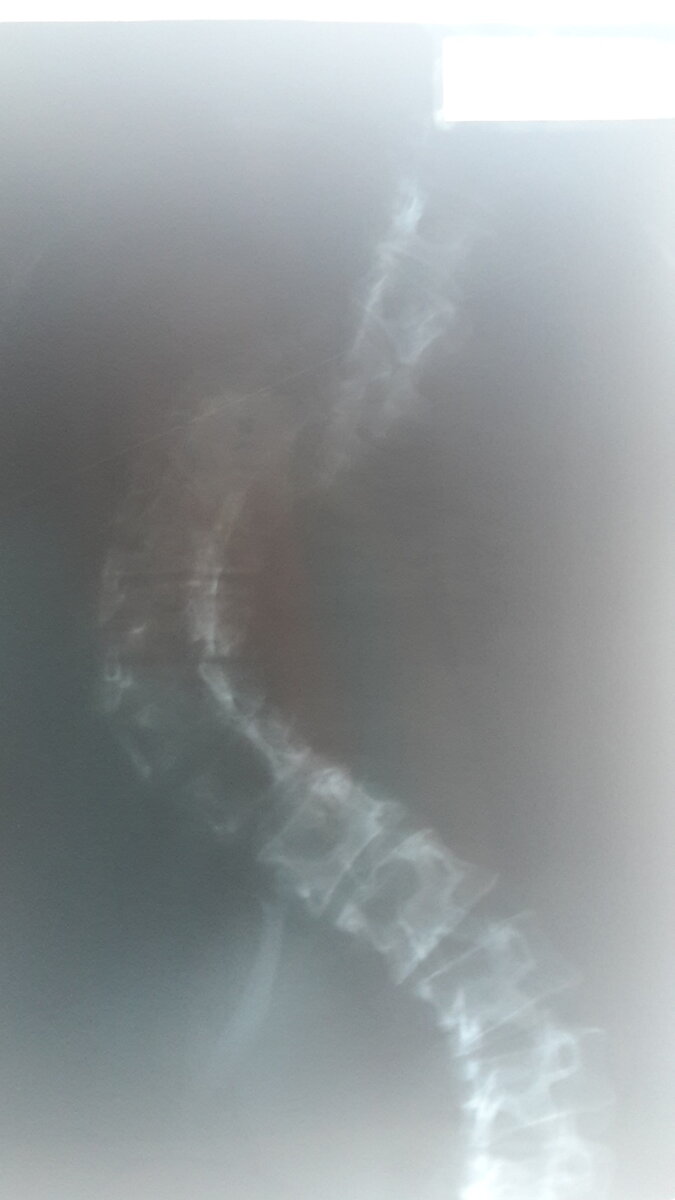

Я инвалид 3 группы по заболеванию сколиоз 4 степени. Сколиоз — искривление позвоночника, при котором он отклоняется от естественной физиологической оси в сторону: от незначительного угла до грубой формы с образованием реберного горба, скручиванием позвонков, деформацией грудной клетки. У меня как раз та серьезная форма, которая видна визуально даже через верхнюю одежду. К косметическому дефекту приобщается смещение внутренних органов, боли в спине, нарушение дыхания, пищеварения и т.п.

Сколиоз 4 степени на снимке